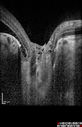

9 year old boy He is having some trouble seeing his gadgets (like his watch). He was diagnosed with morning glory syndrome at about 3 yeras old. This last visit you saw fluid under the retina and asked him to come here. The vision is a little worse. Vision 20/40 right eye; 20/25 left eye. Right eye has serous retinal detachment and evidence of RPE problems from prior fluid.

Optic Nerve Pit Retinal Detachment - SD OCT of Nerve EDI shows Pit548 views9 Year old with morning glory disc who developed nerve pit RD. Raster scans of the optic nerve on EDI setting show the communication between the subretinal space and the fluid around the cerebrospinal fluid surrounding the optic nerve sheath.00000